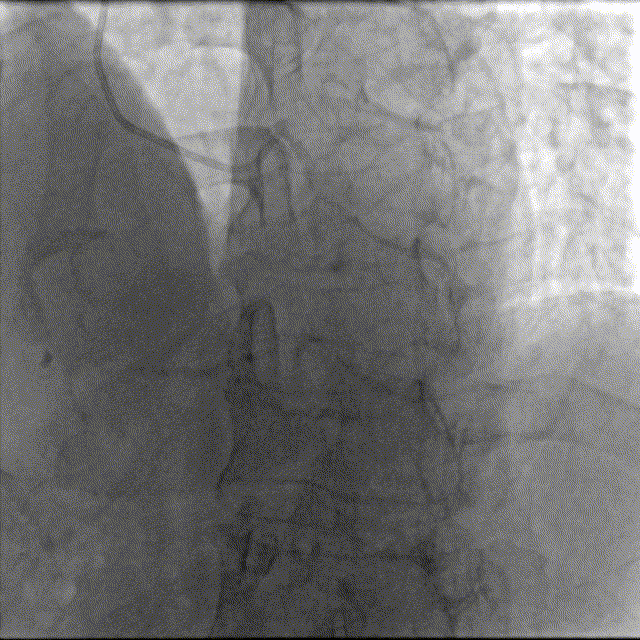

造影如下

患者左主干前三叉1,0,1型病变,主干末端偏心40%狭窄;前降支病变自开口延续至中段,口部80%狭窄,中段80%狭窄,病变位置钙化严重;回旋支近段约30%轻度狭窄,第一及第二钝缘支开口80%局限病变。